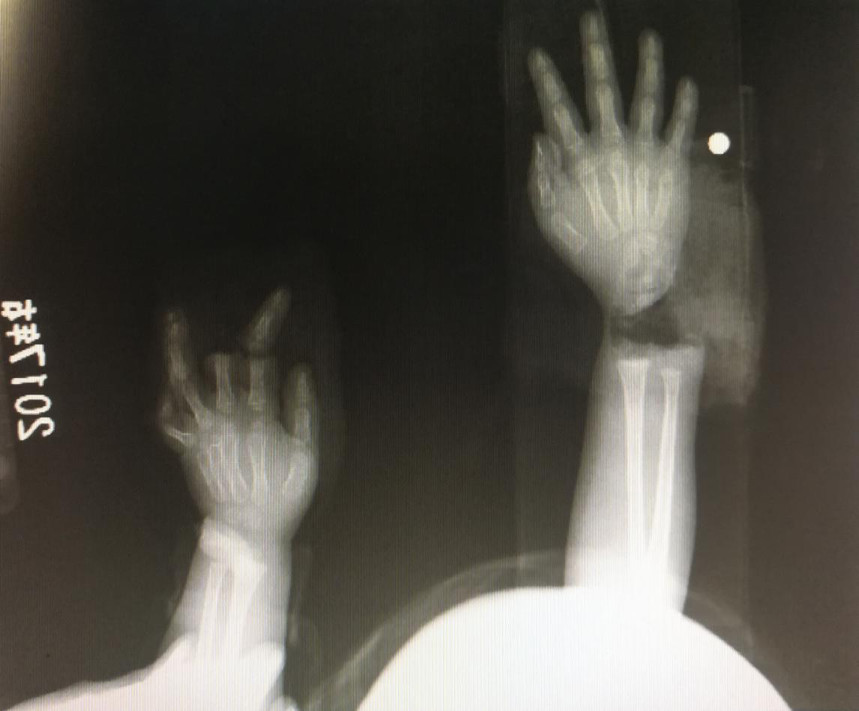

“急診在哪,急診在哪”,伴隨著一聲聲急促的問(wèn)詢,一位年輕女士抱著渾身是血的小孩疾步前往急診室,懷里的小孩在疲憊與疼痛的交織下,時(shí)睡時(shí)醒。鑒于小孩的情況,急診醫(yī)生迅速安排給小孩拍了X光片,影像片結(jié)果顯示小孩左手手腕完全離斷,右手中、食指離斷,距離事發(fā)時(shí)間已經(jīng)3個(gè)多小時(shí),需盡快安排手術(shù)。

經(jīng)過(guò)長(zhǎng)達(dá)5個(gè)多小時(shí)的手術(shù),小宇(化名)終于被送出了手術(shù)室,離斷的手腕和手指均已完成再植,但關(guān)于斷指的存活與否還需要經(jīng)過(guò)一個(gè)十天的觀察期。小宇的主治醫(yī)生是長(zhǎng)沙年輪骨科醫(yī)院手足外科馬思成醫(yī)生,據(jù)馬醫(yī)生介紹,小宇受傷情況比較嚴(yán)重,失血過(guò)多,而且兩個(gè)手都存在完全離斷的情況,手術(shù)時(shí)安排了兩組醫(yī)生同時(shí)進(jìn)行,整個(gè)手術(shù)過(guò)程比較順利,目前小宇還處于觀察期。